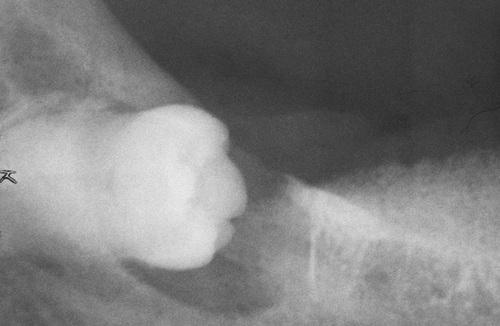

This large, multilocular cyst involves most of the ascending ramus and is growing in an anteroposterior direction.

odontogenic keratocyst (OKC)